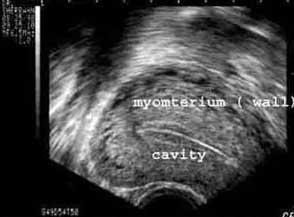

Какво може да се види с ултразвук? Ултразвукът дава ясно изображение на матката и яйчниците. Позволява на лекаря да провери за миоми; кисти на яйчниците; и извънматочни бременности. Също е отличен за ранно диагностициране на бременност. Ултразвуковото изследване обаче не е много добро за оценка на състоянието на тръбите.

Фиг. 2. Ултразвуково сканиране на матката, показващо нормален ендометриум, който се вижда като тройна ивица в центъра на матката